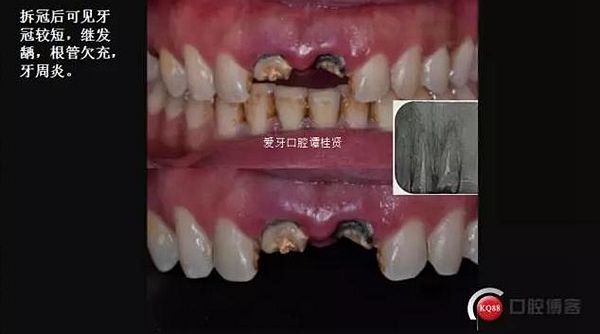

口內(nèi)檢查:很輕易就取下牙冠,均為殘冠殘根且繼發(fā)齲,#21尤為嚴重,已到齦下,牙周探診1.5mm,X線檢查:根尖陰影,欠充。

診斷:#11#21殘根,繼發(fā)齲,輕度牙周炎。

三診 牙周牙髓聯(lián)合治療